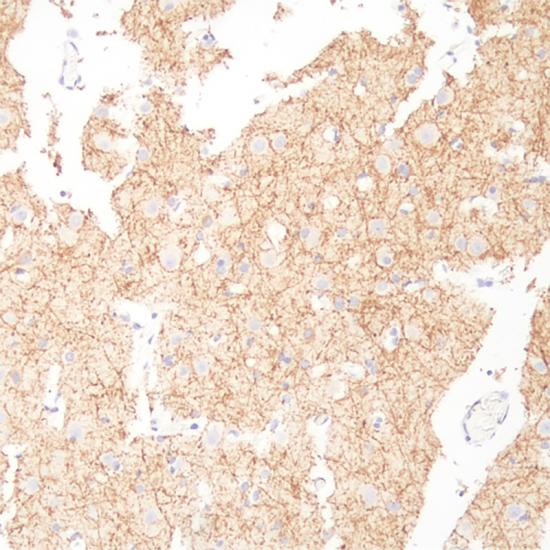

Neurofilament

Neurofilament抗體試劑(免疫組織化學(xué)) 閩廈械備20180252號(hào)

• 陽(yáng)性部位:

細(xì)胞漿

• 陽(yáng)性對(duì)照:

神經(jīng)膠質(zhì)瘤

Neurofilament (NF) 是神經(jīng)元特異性中間絲蛋白,是由三個(gè)不同分子量的亞單位構(gòu)成的多聚 體,以不同的比例分布于中樞、外周神經(jīng)元以及腫瘤中。主要表達(dá)于節(jié)細(xì)胞神經(jīng)瘤,副節(jié)瘤、小腦或外周神經(jīng)母細(xì)胞瘤,腎上腺瘤和外周嗜銘細(xì)胞瘤,有助于神經(jīng)母細(xì)胞瘤和嗜銘細(xì)胞瘤的診斷與鑒別診斷。